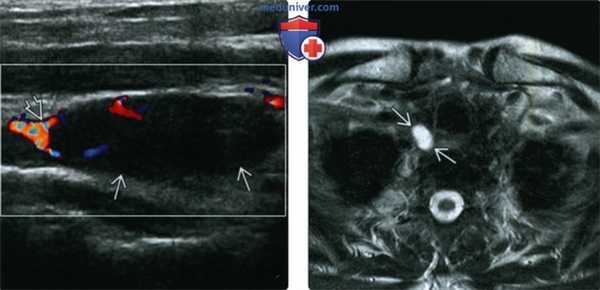

(Справа) УЗИ, аксиальная проекция на уровне перешейка щитовидной железы. Определяется гипоэхогенное однородное образование, расположенное позади правой доли щитовидной железы и смещающее щитовидную железу кпереди. Хотя образование имеет четкие контуры, оно оказалось паращитовидной карциномой. (Слева) Сцинтиграфия с технецием-99 сестамиби, прямая проекция, поздняя стадия. Нормальный захват радиофармпрепарата обеими поднижнечелюстными железами, а также патологический очаг в нижнем отделе шеи, представляющий собой рак паращитовидной железы. Аденома паращитовидной железы выглядела бы аналогично.

(Слева) Сцинтиграфия с технецием-99 сестамиби, прямая проекция. На шее имеется лишь один небольшой участок накопления радиофармпрепарата. Сестамиби захватывается и щитовидной, и паращитовидной железами; но данному пациенту в прошлом выполнялась тиреоидэктомия. На отложенных изображениях также отмечалось накопление радиофармпрепарата.

(Справа) Отложенная сцинтиграфия с технецием-99 сестамиби, определяется накопление препарата у нижнего правого полюса щитовидной железы, которое характерно для паращитовидной аденомы.

(Слева) КТ с КУ, аксиальная проекция, артериальная фаза. Визуализируется характерная «полярная артерия», которая кровоснабжает паращитовидную аденому, расположенную книзу от щитовидной железы, в жировой клетчатке верхнего средостения.

(Справа) КТ с КУ, аксиальная проекция, артериальная фаза. Визуализируется типичная паращитовидная аденома, активно накапливающая контрастное вещество. На выполненных ранее УЗИ и сцинтиграфии с сестамиби визуализировать аденому не удалось. На поздней стадии (венозной) КТ аденома была практически не видна, поскольку ее плотность была почти идентична плотности пищевода. Это говорит о том, как важно оценивать паращитовидные железы именно в артериальную фазу.

(Слева) Допплерография, продольная проекция. Определяется гипоэхогенная аденома паращитовидной железы с участком гиперваскуляризации у ее полюса.

(Справа) При МРТ Т2ВИ в аксиальной проекции визуализируется округлое образование с однородным гиперинтенсивным сигналом, более интенсивным по сравнению с щитовидной железой. Неоднородное строение образования стало очевидным после введения гадолиния (здесь не показано). Четкие контуры говорят о доброкачественной природе образования.